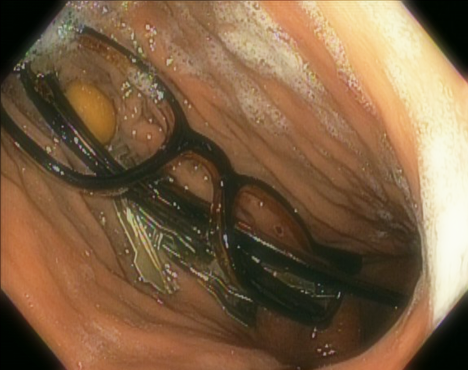

因此,大多数胃内异物可以不予处理、两天内注意观察粪便中是否有异物排出,除非是某些可能造成肠子穿孔的尖锐物体、或者长期逗留会腐蚀胃粘膜的硬币或者电池。但是,假如异物实在太大,尺寸超过5厘米×2厘米,它就基本上不可能通过胃的出口幽门了。

一个55岁的抑郁症男子吞下了一整幅老花眼镜和一堆金属零件,最后被灵巧的医生通过内镜取出。图片来源 Endoscopy